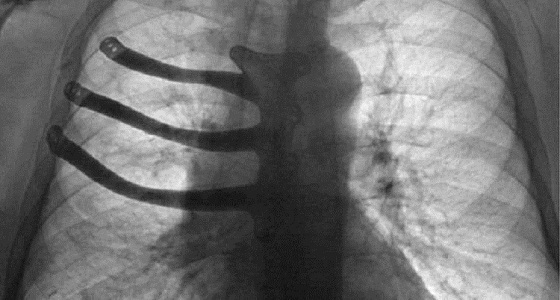

لأول مرة.. طباعة ” 3D ” لقفص صدري مستأصل في بريطانيا